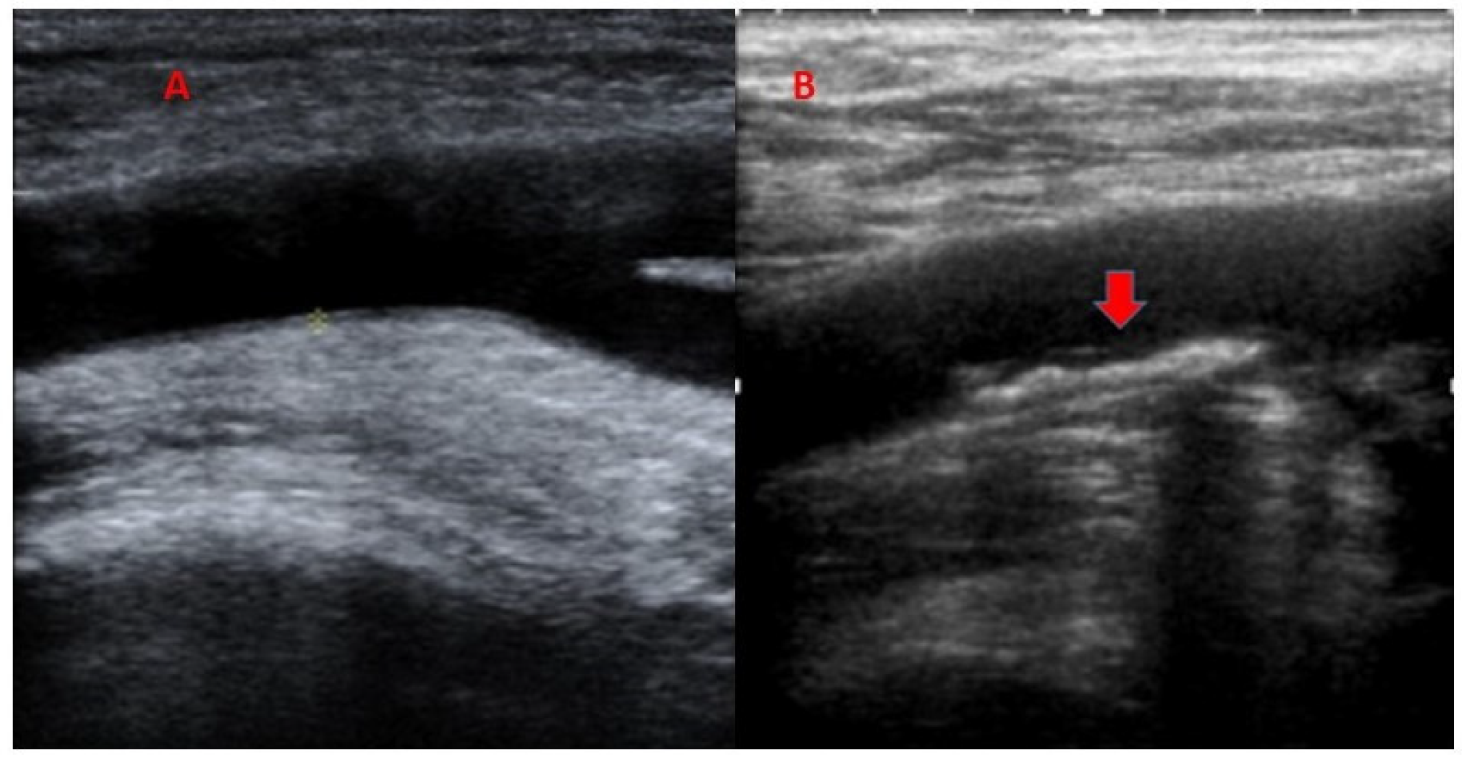

2.2. Subclinical Arteriosclerosis

2.3. Liver Steatosis

| Ultrasound | ||||

| RCCA | ||||

| IMT (mm) | 0.78 (0.17) | 0.80 (0.19) | 0.76 (0.15) | |

| Plaque (%) | 24 (16) | 10 (19) | 14 (28) | |

| LCCA | ||||

| IMT (mm) | 0.79 (0.17) | 0.80 (0.17) | 0.78 (0.17) | |

| Plaque (%) | 18 (12) | 8 (15) | 10 (20) | |

| RFA | ||||

| IMT (mm) | 0.82 (0.35) | 0.80 (0.36) | 0.84 (0.34) | |

| Plaque (%) | 27 (18) | 9 (17) | 18 (36) | <0.05 |

| LFA | ||||

| IMT (mm) | 0.84 (0.34) | 0.85 (0.35) | 0.83 (0.32) | |

| Plaque (%) | 89 (20) | 15 (28) | 15 (30) | |

| Total Plaques | 32 (21) | 32 (15) | 57 (28) | <0.05 |

| Averaged IMT | 0.81 (0.20) | 0.81 (0.20) | 0.80 (0.19) | |